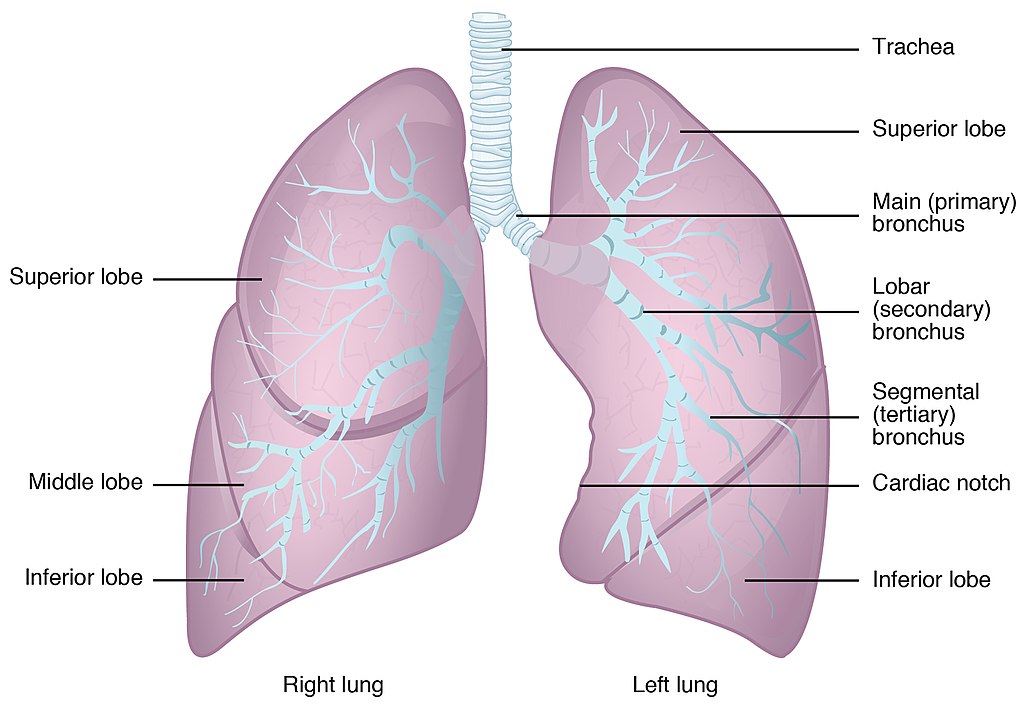

1 – Review of Respiratory System Anatomy